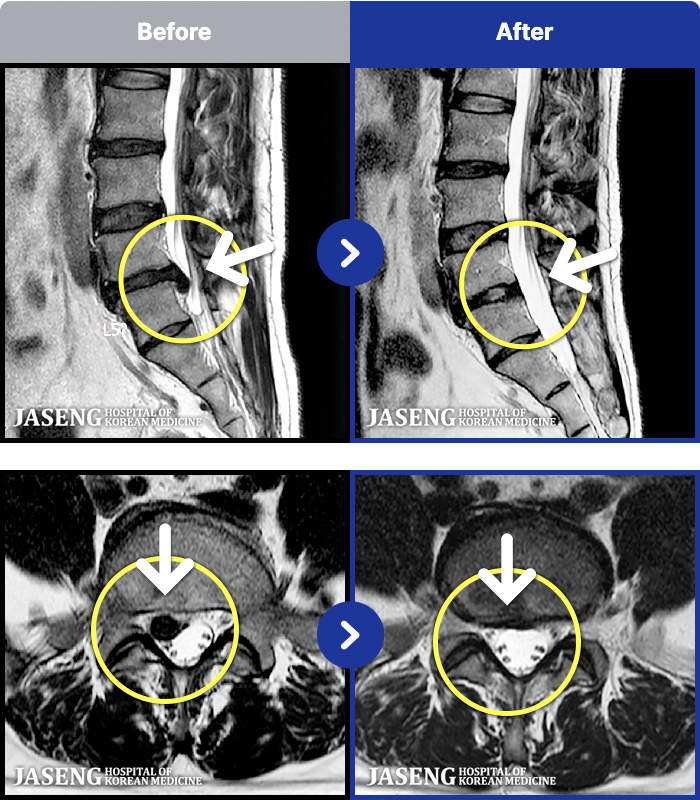

MRI ġ

1,240 MRI ũ ʸ Ȯϼ.

㸮 ϻ .